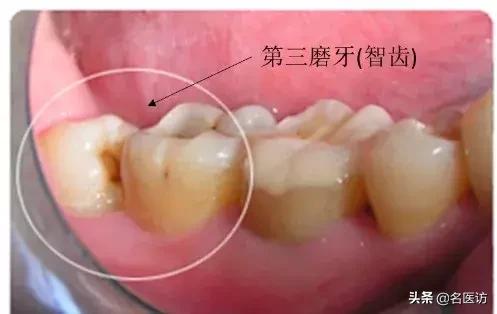

原来,智齿,学名叫第三磨牙,通常在人 17~25 岁时出现在口腔中。大部分人有 4 个智齿(上颌 2 个,下颌 2 个),但是也有人可能只有 1~3 个甚至没有。

当这些智齿突破牙龈,它们便被称为“萌出”。如果智齿不能萌出,或只能部分萌出牙龈,就叫做“阻生”。